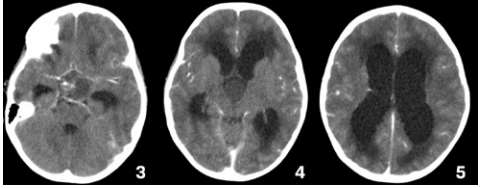

Caso clínico 3 para as questões 27 e 28.

Criança feminina, 04 anos, é encaminhada de Unidade de Pronto Atendimento (UPA) de Olinda-PE com história de cefaleia acompanhada de vômitos, inapetência e sonolência há 03 dias, sendo solicitado parecer da neurocirurgia. Ao exame: ECG Pediátrica de 13 (Resposta Ocular = 3 + Resposta Verbal = 4 + Resposta Motora = 6), isocórica e RFM lentificado bilateralmente, mobilizando todos os membros e reflexos presentes e simétricos.

Seguem, abaixo, as imagens de TC de crânio sem e com contraste da paciente, com índice de Evans de 0,41.

Pelas imagens mostradas, qual o mais provável diagnóstico e o objetivo do tratamento para a paciente?

Caso clínico 3 para as questões 27 e 28.

Criança feminina, 04 anos, é encaminhada de Unidade de Pronto Atendimento (UPA) de Olinda-PE com história de cefaleia acompanhada de vômitos, inapetência e sonolência há 03 dias, sendo solicitado parecer da neurocirurgia. Ao exame: ECG Pediátrica de 13 (Resposta Ocular = 3 + Resposta Verbal = 4 + Resposta Motora = 6), isocórica e RFM lentificado bilateralmente, mobilizando todos os membros e reflexos presentes e simétricos.

Seguem, abaixo, as imagens de TC de crânio sem e com contraste da paciente, com índice de Evans de 0,41.

Como se calcula o índice de Evans que foi de 0,41 e o que se fazer pela urgência nesse caso, respectivamente?